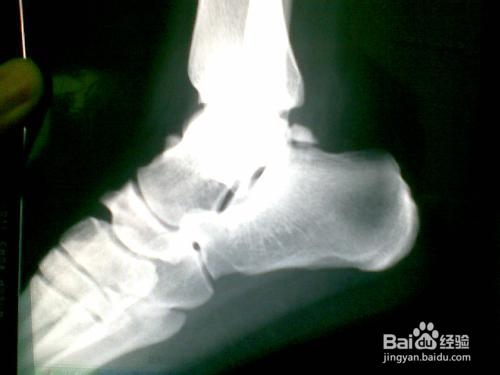

1、首先确定有无骨折,拍X光片。